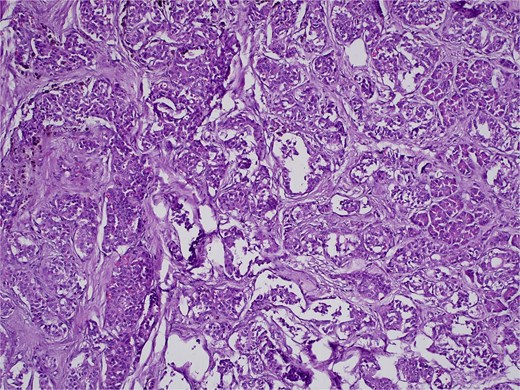

On 27 January 2025, the patient underwent a Whipple procedure (pancreaticoduodenectomy). The surgery included cephalic pancreatectomy with reconstruction through hepaticojejunostomy and gastrojejunostomy in a Roux-en-Y configuration. Gross pathology revealed a firm, white-yellow, indurated mass in the pancreatic head measuring 3.7 × 3.5 × 3 cm with irregular borders and central hardness (Fig. 4). Histopathological analysis confirmed a Grade 1 neuroendocrine tumor (insulinoma), with a Ki-67 index of 2%. The tumor showed direct extension to adjacent pancreatic tissue, the duodenal muscularis propria, the adventitia, and the muscularis of the common bile duct. Five peripancreatic lymph nodes were dissected, three of which were positive for metastases (Figs 5–9).

H&E stain, 100× magnification. Diffuse infiltration of pancreatic parenchyma by tumor cells with desmoplastic stroma.

H&E stain, 100× magnification. Irregular clusters of neoplastic cells with vascular invasion.

H&E stain, 100× magnification. Papillary and trabecular architecture with minimal atypia and characteristic “salt and pepper” chromatin.